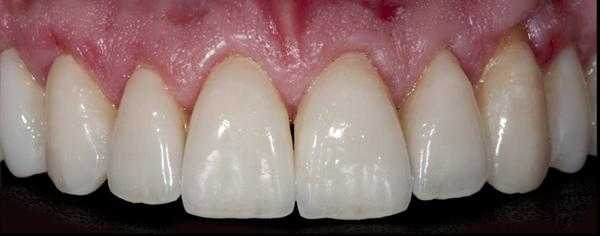

Пациент обратился за помощью с несколькими основными жалобами, главной из которых являлась эстетическая дилемма: ему не нравился цвет, размер и форма зубов (фото 1). При этом он также желал по возможности закрыть диастему между 10 и 11 зубами. Он также был обеспокоен «объемом» собственной улыбки и хотел расширить форму зубной дуги так, чтобы улыбка казалась более полной. Во время стоматологического осмотра было установлено, что пациент имел умеренную степень стирания режущих и окклюзионных поверхностей, легкую генерализированную форму рецессии с локализированной умеренной рецессией в области первых моляров верхней челюсти. Большинство боковых зубов имели амальгамные реставрации небольших и средних размеров с признаками вторичного кариеса. На 18 и 29 присутствовали металлокерамические конструкции. Все передние зубы верхней челюсти и несколько передних зубов нижней челюсти имели композитные пломбы в интерпроксимальных зонах, которые со временем изменили свой цвет.

Фото 1. Вид зубов пациента перед вмешательством.

Фото 26. Вид после вмешательства.

Фото 27. Фронтальный вид после вмешательства.